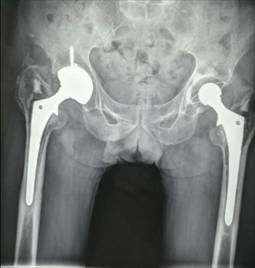

全髋关节置换术治疗股骨头坏死

优点:手术成熟,疗效确切。

术前术后对比

全髋关节翻修术